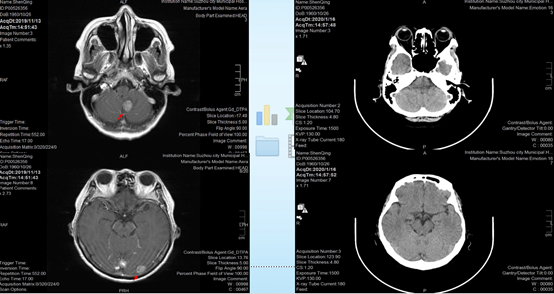

2020-03-23,患者再次复查CT,发现胸膜下结节较前增大,右下肺病灶继续缩小,但患者胸腔积液明显增多,疗效评估疾病进展(PD)。

头颅增强MRI没有发现头部转移灶,疗效评价疾病稳定(SD)。

由于患者脑部转移灶控制良好,因此继续选择继续奥希替尼80mg qd治疗,并予以胸腔闭式引流,胸水送检制作细胞蜡块。同时,患者抗拒化疗,因此选择贝伐珠单抗500mg静滴2周期。

2020-05-07,患者复查过程中,发现胸腔积液进一步增多,胸膜下病灶进一步增大。随即调整治疗方案,予以奥希替尼80mg qd,再次胸腔闭式引流,胸水送检制作细胞蜡块,胸腔内注射恩度,予培美曲塞、卡铂化疗2周期。

将患者两次的胸水细胞蜡块以及淋巴结穿刺组织再次进行基因检测,结果仍旧是EGFR 19外显子突变,但不同样本之间的丰度不同。

2020-08-03,患者再次入院复查,发现胸膜下病灶较前缩小,胸腔积液也有一定好转,但持续存在。